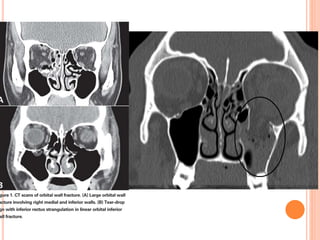

Wall and floor fractures

 medial wall- lamina papyracea

 orbital floor- blow out vs rim involvement